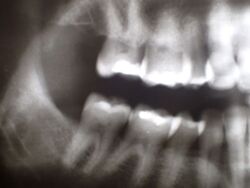

In diesem Zusammenhang wurde heute noch ein Übersichtsröntgenbild erstellt, dass einen ganz typischen, aber häufig nicht bekannten Befund mit sich bringt.

Obwohl die Patientin erkennbar eine gute Mundhygiene beteibt, zeigt sich im gesamten Oberkiefer und hier vor allem im Bereich der Backenzähne ein ausgeprägte und altersuntypisch weit voran geschrittener Knochenabbau.

Fast noch schlimmer: Der Patientin ist das nicht bekannt.

Das Typische an diesen Zuständen besteht darin, dass der Knochen im Unterkiefer weitgehend normal erscheint, was bene gerade dafür spricht, dass es sich um kein mundhygienebedingtes Problem des Kieferknochenabbaus handelt.

Sollte über die Funktionsdiagnostik hinaus in diesem Fall eine Funktionstherapie zustande kommen, wäre deren Ziel nicht nur die Beseitigung/Linderung der bekannten funktoinellen Beschwerden, sondern darüber hinaus der Stopp des anhaltenden alveolären Knochenabbaus.